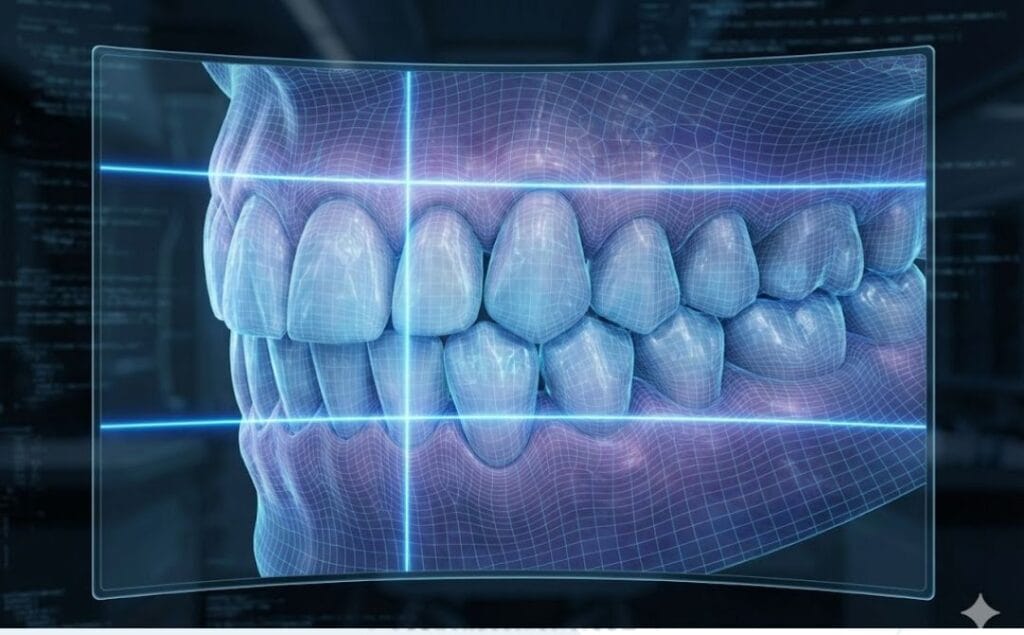

- تصميم الابتسامة الرقمي: رؤية النتيجة المتوقعة قبل بدء العملية (DSD).